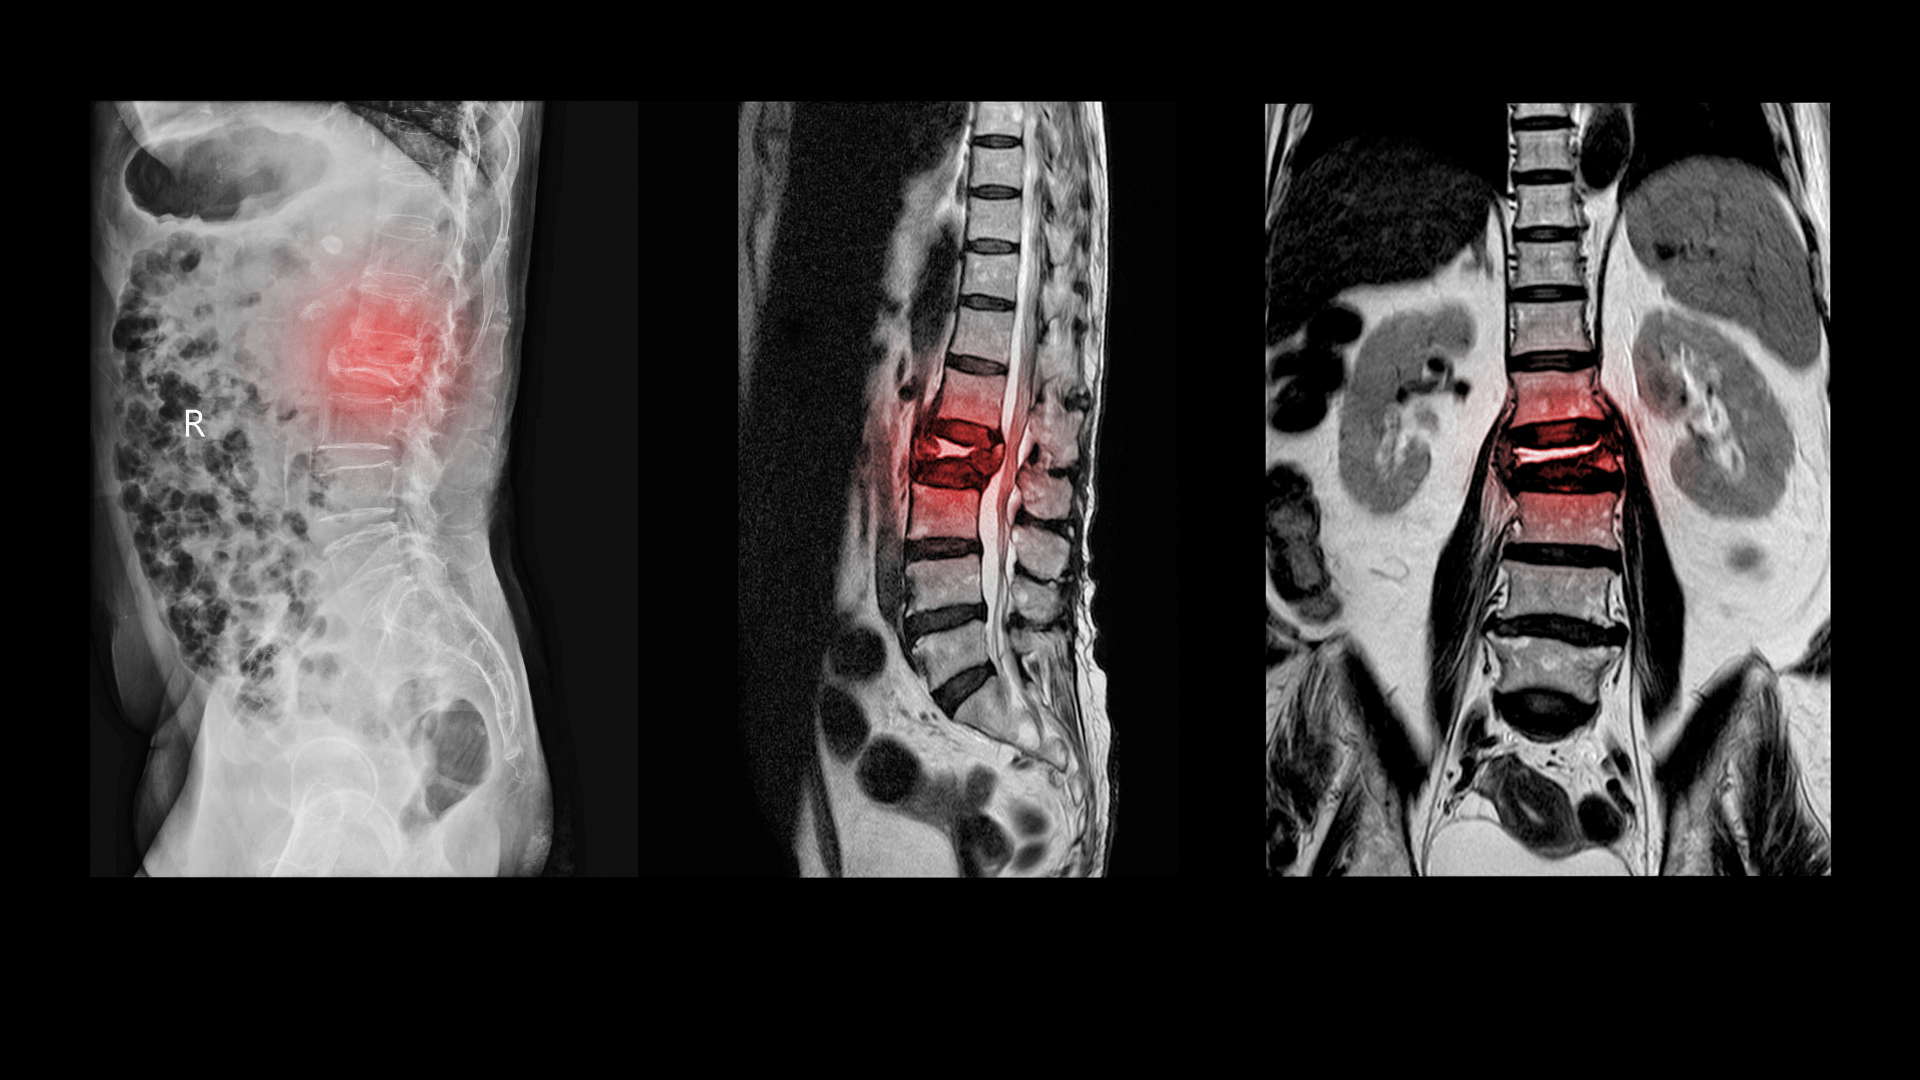

Az alábbiakban megvizsgáljuk a gerinccsatorna szűkületet, tüneteit, a szükséges vizsgálatokat és a lehetséges...

A gerincsérv Magyarországon mondhatni népbetegségnek számít, ez a második leggyakrabban előforduló p...

A gerincsérv vizsgálat kiemelten fontos, hiszen a probléma a korai fázisban még visszafordítható. Ebben...

A cikkben a gerincsérv kezelése lesz a górcső alatt. Megtudja, milyen módszerekkel lehet eredményesen...